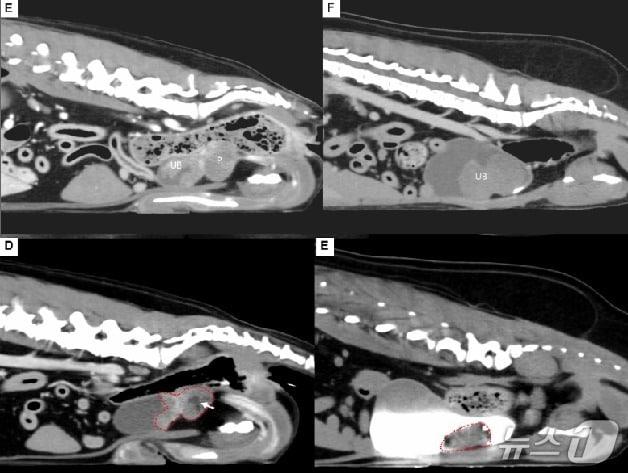

색전술로 종양 치료 전(상단)과 후(하단) CT 촬영 모습(해마루 제공) ⓒ 뉴스1